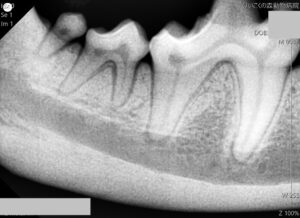

口の中のレントゲンも撮影します。この検査では表面からの見た目だけではわからない歯の根の周囲の様子が確認できます。口の中に専用のセンサーを挿入して撮影するため、犬にとってストレスにならないよう麻酔をかけた状態で行う必要があります。同時に歯を1本1本触り、歯肉の溝の深さを測って深い歯周ポケットができていないか確認もします(プロービング)。

結果として、昨年から歯周病が進行した箇所はみられず、抜歯などの必要はありませんでした。歯肉の溝含めて徹底的なスケーリング治療を行って終了です。